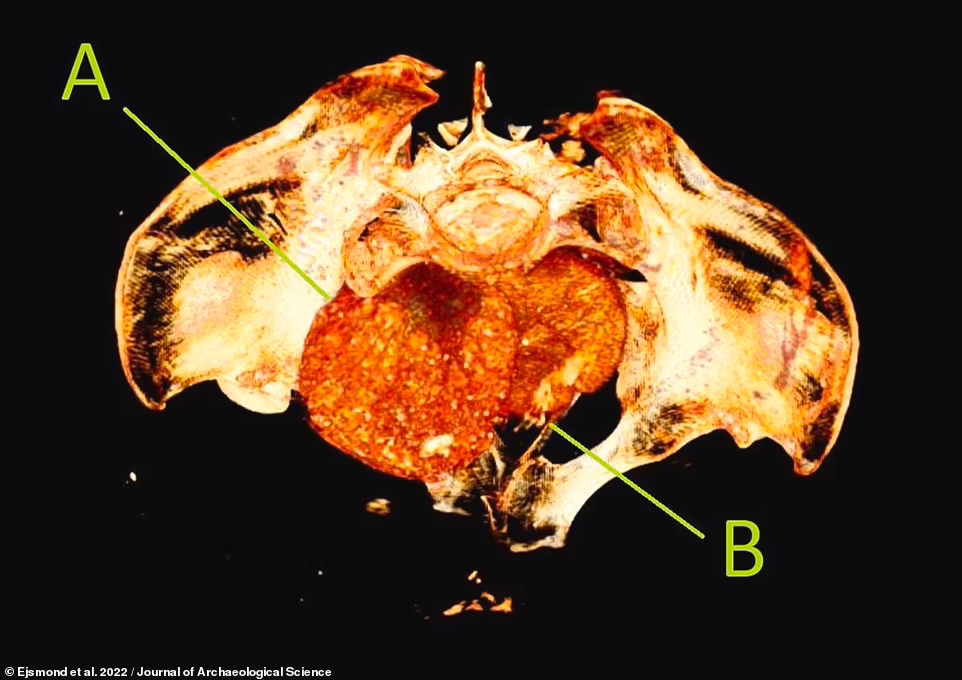

玛尔泽娜博士的研究团队表示,胎儿在子宫内“被腌制”,尸体血液的pH值明显下降,变得更加酸性,氨和甲酸的浓度随着时间的推移而增加,胎儿所处的环境与保存古代尸体的沼泽环境相当。

由于神秘女士的尸体在分解过程中的酸化会使胎儿的骨骼脱矿,这使得胎儿很难首先被发现。

由于长期浸泡在酸性环境中,胎儿的骨骼已经溶解

研究小组解释说,在木乃伊中,从胎儿骨骼中浸出的矿物质会沉积到胎儿的组织和周围的子宫中,使两者具有更高的辐射密度,从而在CT扫描中呈现出不同的外观。